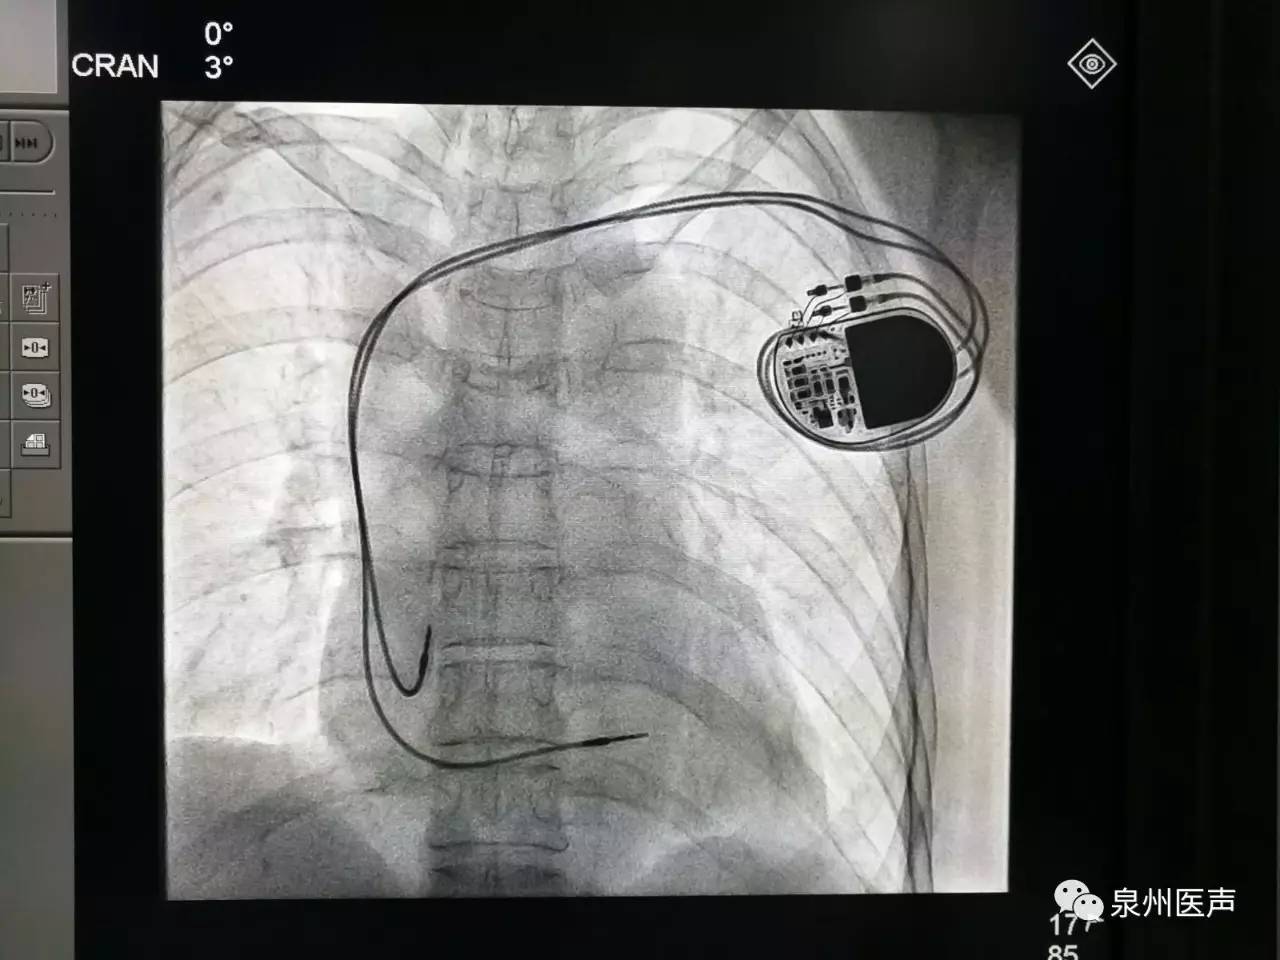

微創(chuàng)、樂普、先健填補(bǔ)國產(chǎn)起搏器市場空白,釋放哪些信號?

世界最小起搏器,正式進(jìn)入中國市場!

最高級別!美敦力緊急召回1.3萬個(gè)雙腔植入式心臟起搏器!